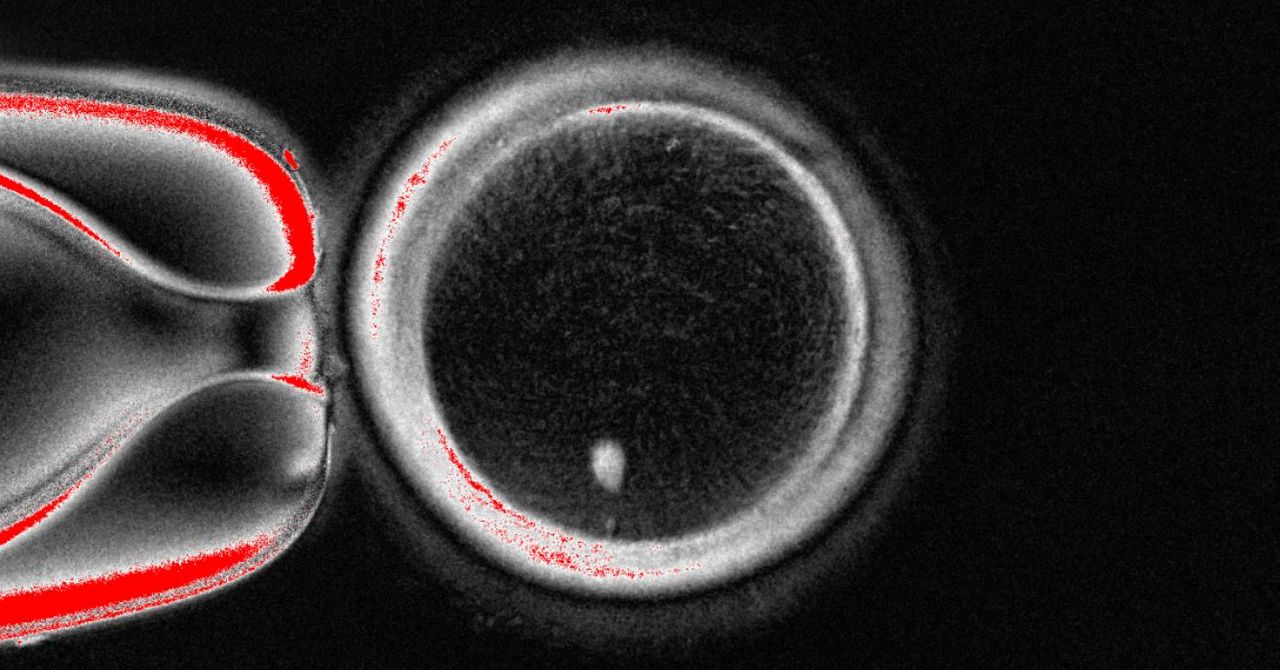

“O maior desafio é como fazer com que esse ovo extrate metade de seus cromossomos – e a metade correta”, diz Amato. “Ainda não estamos lá.” A equipe apelidou de sua técnica de “mitomeiose” e está tentando entender melhor como os cromossomos gostam de emparelhar e como eles segregaram para encontrar uma maneira de induzir experimentalmente essas condições.

Em 2016, um grupo de pesquisadores japoneses liderados pelo pesquisador de células -tronco Katsuhiko Hayashi relatou que eles Produzido filhotes de mouse saudável Depois de fazer ovos de mouse inteiramente em um prato de laboratório. Mais tarde, eles geraram ovos de camundongo usando células dos machos e, como resultado, criaram filhotes com dois pais. Esses avanços foram alcançados reprogramando as células da pele de camundongos adultos em células -tronco e depois persuadindo -as a se transformar em ovos e espermatozóides.

Mitinori Saitou na Universidade de Kyoto documentou pela primeira vez em 2018 como sua equipe transformou células sanguíneas humanas em células -troncoque eles então transformaram em ovos humanos, mas eram imaturos demais para serem fertilizados para fazer embriões.